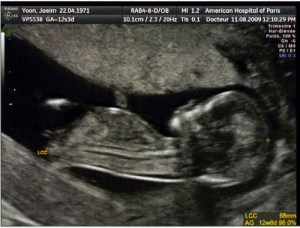

Aujourd’hui, dans la moitié des cas, il est possible de connaître le sexe, du moins son estimation, dès 12 semaines d’aménorrhée (SA). L’obstétricien observe alors la forme du « turbercule génital ». En fonction de son inclinaison, il pourra vous dire si c’est plutôt une fille (bourgeon presque parallèle au dos de l’enfant, angle inférieur à 10%), ou un garçon (angle de 30% environ par rapport au dos). Mais pour que cela soit réalisable, il faut que les clichés soient bons. Et la chose se révèle donc plutôt corsée quand vous avez un bébé qui prend votre utérus pour une piscine olympique en plein championnat… Autant l’avouer de suite: nous n’avons rien su à l’écho des 12 SA.

Quand vous loupez ce rendez-vous avec la « vérité », vous pouvez éventuellement vous rattraper sur l’écho de contrôle des 17-18 SA. A ce moment, le sexe commence à se dessiner et l’estimation est plus précise. Cependant, seule une partie des obstétriciens réalisent cette échographie. Si vous êtes suivis par une sage-femme, vous devrez attendre la prochaine échographie : 22 SA. Ce fut notre cas.

Et croyez-moi, voir « un trait » là où l’on pensait voir « quelque chose dépasser », c’est une sacrée surprise… Bienvenue ma fille!